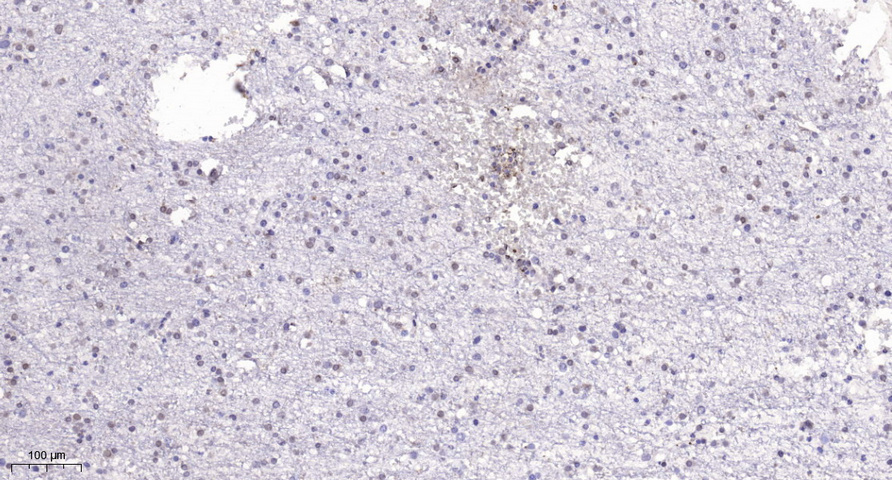

Immunohistochemical analysis of paraffin-embedded human brain. 1, Tris-EDTA,pH9.0 was used for antigen retrieval. 2 Antibody was diluted at 1:200(4° overnight.3,Secondary antibody was diluted at 1:200(room temperature, 45min).